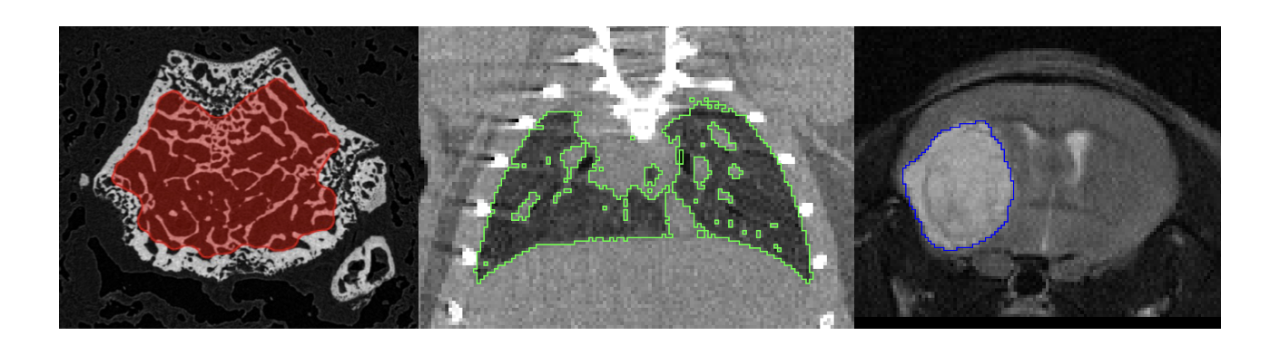

pmod’s tools provide comprehensive workflows for post-processing and quantification of imaging data for fundamental oncology research, development of radiotracers and theranostics, and in clinical research studies. Imaging scientists can trust pmod to reproducibly read their data, interpret the meta-data/units and help users calculate statistics such as SUV for their studies and publications.

• Multimodality segmentation tools – comprehensive semi-automated and manual tools for precision and reproducibility

• Flexible switching between 3D and 4D datasets – direct output of time activity curves